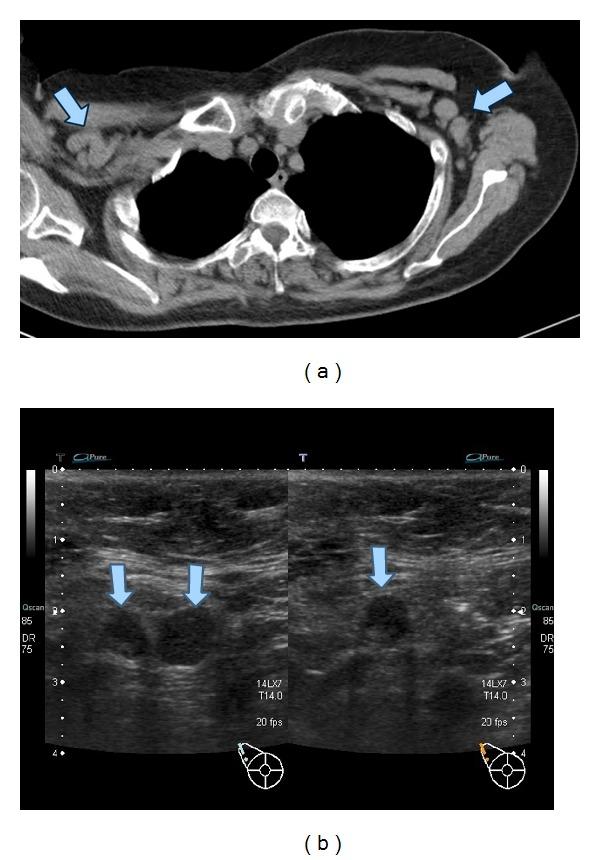

A 57-year-old woman with rheumatoid arthritis (RA) and limited systemic sclerosis (lSSc) was suspected to have lymphadenopathy and primary biliary cirrhosis (PBC). Lymph node biopsy showed reactive follicular lymphadenopathy with intrafollicular plasmacyte infiltration that was interleukin-6 positive by immunohistostaining. Because of gradually worsening arthritis, tocilizumab was administered and arthritis improved markedly. Interestingly, lymphadenopathy and PBC improved simultaneously. This suggested that interleukin-6 might play an important role in reactive lymphadenopathy and PBC associated with RA/lSSc.

一名患有类风湿关节炎(RA)和局限性系统性硬化症(lSSc)的57岁女性被怀疑有淋巴结病和原发性胆汁性肝硬化(PBC)。淋巴结活检显示反应性滤泡性淋巴结病,伴有滤泡内浆细胞浸润,免疫组化染色显示白细胞介素-6呈阳性。由于关节炎逐渐加重,给予托珠单抗治疗,关节炎明显改善。有趣的是,淋巴结病和PBC同时改善。这表明白细胞介素-6可能在与RA/lSSc相关的反应性淋巴结病和PBC中起重要作用。